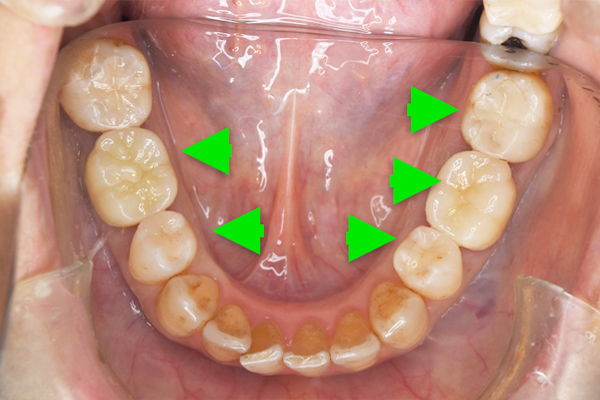

![]() |

|---|

| 主 訴 | 金属の見ためを改善したい |

|---|---|

| 治療期間 | 約2ヶ月 |

| 治療費 | セラミックインレー2本、 オールセラミッククラウン2本 511,500円(税込) |

| 治療内容 | 古い金属を見た目が自然で、虫歯にもなりにくいセラミックで治療しました。 |

| 治療上のリスク | 仮歯の間は噛み合わせに違和感を感じる場合が あります。 セラミックは稀に欠ける場合があります。 |